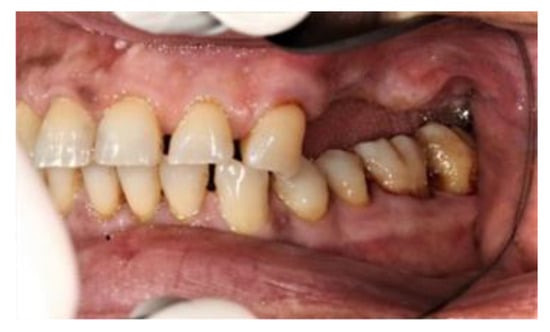

2. Case Report

The subject involved in this clinical study was a healthy woman, 54 years old. The request of this patient was to improve her mouth both functionally and aesthetically, which was altered because of the partial edentulism (Kennedy Class II). She asked to avoid any invasive surgery. During the anamnesis, she declared not to be affected by any systemic pathology (e.g., diabetes, hypercholesterolemia or hypertension). She also declared not to be affected by an allergy to any medication or similar drugs; she declared not to be subjected to any pharmacologic treatment except some analgesic therapy to treat sporadic headaches. The patient claimed to smoke 20 cigarettes a day for more than 20 years. The next step was to perform an objective examination, associated with a series of intraoral pictures (Figure 1, Figure 2, Figure 3, Figure 4 and Figure 5) and to the analysis of a radiographic exam (orthopantomography, Figure 6) that was acquired 10 months earlier when the same subject underwent the therapy and the teeth extraction 4.7–4.8. The objective examination showed poor oral hygiene, with plaque accumulation as well as the presence of many pigmentations due to excessive smoking. The radiography showed bilateral bone atrophy together with periodontal damage for most of the residual dental elements. These conditions represented a limitation to the insertion of implants for a fixed prosthesis.

Figure 2. Right lateral view.

Prosthesis 03 00038 g002

Figure 3. Left lateral view.

Prosthesis 03 00038 g003